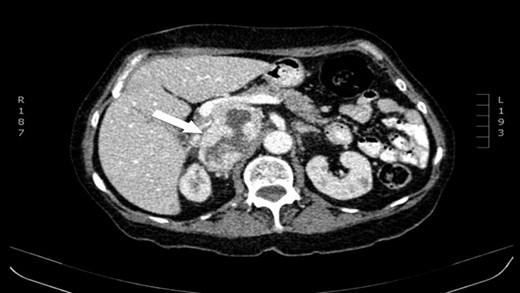

The authors report a case of a 64-year-old female, with no relevant family history and a past medical history of recently diagnosed supraventricular tachycardia, arterial hypertension, type 2 diabetes mellitus, euthyroid multinodular goiter and chronic venous insufficiency. She was referred to our Institution from other Hospital where she went due to paroxysms of palpitations, headache and diaphoresis, that led to biochemical investigation that was remarkable for: total plasmatic cathecolamines: 73 747 ng/L (normal range (NR) <598 ng/L), plasmatic noradrenaline: 73 589 ng/L (NR <420 ng/L), adrenaline: 130 ng/L (NR <84 ng/L), plasmatic dopamine: 28 ng/L (NR <94ng/L), aldosterone: 87,5 ng/dL (NR 4–31 ng/dL), plasmatic renin activity: 33 ng/mL/h (NR 0,5–4 ng/mL/h), Vanylmandelic acid: 39,2 mg/24 h (NR <13,6 mg/24 h). Abdominal contrast enhanced CT scan revealed a large (70 × 35×78 mm3), hyperdense (20 HU) right adrenal mass. Abdominal magnetic resonance (MRI) also described an adrenal mass with 66×33 mm2, suggestive of pheocromocitoma (slightly hypointense on T1 and markedly hyperintense on T2 weighted imaging). No vascular nor locoreginal lymph node involvement were found and the left adrenal was radiologically normal. The patient underwent genetic testing with next generation sequencing, that excluded mutations of the succinate dehydrogenase (SDHB, C, D and A), MEN2, VHL, Neurofibromatosis type 1 genes. Genetic testing for MAX and TMEM127 were not performed due to institutional unavailability. Pre-operative pharmacological therapy was initiated with phenoxybenzamine (10 mg twice a day), followed by bisoprolol (20 mg/day) and amlodipine (5 mg/day), which rendered the patient fit for surgery. The patient underwent transperitoneal laparoscopic right adrenalectomy. Intraoperatively, a hipervascularized right adrenal gland with adhesions to the upper pole of the kidney was identified and excised, with no complications recorded. In the immediate post-operative period, antihypertensive drugs were stopped and blood pressure remained normal until the second post-operative day, when hypertension and tachycardia recurred, leading to urinary metanephrine reevaluation on the 10th post-operative day. The results were highly suggestive of disease persistence (urinary normetanephrines >10 500 ng/L (NR <600 ng/L)). Histology revealed no signs of neoplasia. Abdominal CT scan revealed the persistence of a solid heterogeneous nodule, with 70 × 49 × 87 mm3 (AP × T × L) adjacent to upper right renal pole, with peripheral contrast enhancement and central necrosis (Figs 1–3). This findings suggested abdominal paraganglioma (of the organ of Zuckerkandl). Due to the higher malignant potential of paragangliomas, an 123I-MIBG scintigraphy was performed, excluding metastatic disease.

CT scan (coronal) of the heterogenous solid nodule (white arrow).